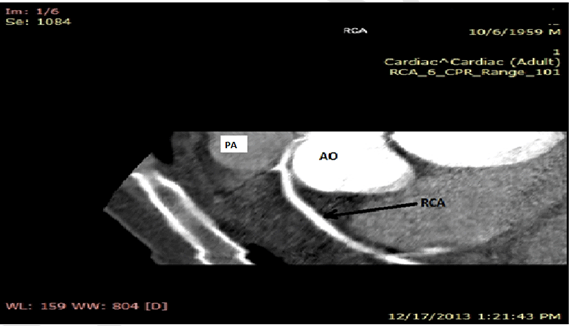

At physical examination he was right hand monoparesis, irregular cardiac rhythm and an accentuated second heart tone at the mitral valve area. Blood pressure was 120/80 mmHg. Heart rate was 100 beats per minute. Electrocardiogram showed atrial fibrillation trans-thoracic echocardiography showed calcified mitral stenosis, with an anatomical area of 1.1 cm2, aortic regurgitation, left atrial dilatation and slight tricuspid valve regurgitation. Pulmonary artery systolic pressure was 30 mmHg (Figure 1).

Figure 1: Transthoracic echocardiography, parasternal short axis view. Anatomical area of the mitral valve is depicted. Mitral valve (particularly the posterior cusp) is calcified. Maximal Gradient was 11.6 mmHg; mean gradient 5mmHg.